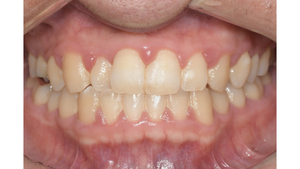

Before

症例

after

基本情報

年齢・性別 41歳・男性

主訴 主訴:歯ぐきから出血する

治療部位:全顎

治療内容 1.歯周ポケット検査、資料取り(レントゲン写真14枚・口腔内写真)、歯磨き指導

2.歯磨き指導チェック、縁上の歯石除去

3.縁下の歯石除去4回

4.再評価(歯周ポケット検査・レントゲン写真14枚・口腔内写真)

5.メインテナンス

治療期間 1日

治療費 合計:14,160円

内訳(全て保険診療3割負担)

・初診検査、歯磨き指導、縁上の歯石除去:3,630円

・レントゲン写真、縁下の歯石除去①:3,040円

・縁下の歯石除去②:1,530円

・歯磨き指導チェック、縁下の歯石除去③:2,070円

・縁下の歯石除去④:1,530円

・再評価:2,360円

(2022年5月現在現在)

リスク・副作用 ・歯石除去後すぐは歯ぐきを触っているため歯ぐきに違和感や痛みを感じる場合がある

・歯石除去により今まで腫れていた歯ぐきが引き締まり歯ぐきが下がる可能性がある

・歯ぐきが引き締まって下がることにより歯面が今までより露出し知覚過敏の症状がでる可能性がある

・歯石除去後、歯磨きを怠ると細菌が歯周ポケットのより深部まで入ってしまうため歯周病が悪化してしまう可能性がある

・一度歯周病になると再発しやすい為、定期的なメインテナンスが必要になります

治療方針 1.歯磨き指導

2.歯ぐき上の歯石除去

3.歯ぐき下の歯石除去

4.再評価

5.定期的なメインテナンス

特記事項 ・着色除去(PMTC)は自費治療のため希望しませんでした。

・右下7番の歯周ポケット5mmは親知らずの関係もあり、このまま維持していくことを説明しています。

・他4mmの歯周ポケットに関しては歯垢が少し残っていた為、再度歯磨き指導と、縁下の歯石を確認して様子をみることにしました。

担当者所見 全体的に出血が見られたのと、奥の歯ぐきは炎症があり歯周ポケットが深かった為、まずは歯ブラシの当て方+歯間ブラシ3Sサイズを使用して頂き炎症を落ち着かせました。

両方毎日使用して頂いた為、スムーズに歯周病治療を行うことができました。毎日のホームケアが不十分だと、なかなか結果に繋がらず、治療期間も長くかかってしまう為、患者様の協力が歯周病治療を成功させるためにはかなり重要になっていきます。

そして一度病気になった歯ぐきは再発しやすい為、今後は3ヶ月に1度の定期的なメインテナンスで、この状態を維持できるよう一緒に管理していきます。